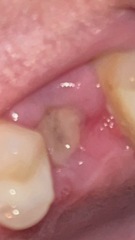

Had lower right molar yanked out in a tug of war battle 4 days ago. Up until today there was a very obvious grey jelly goo level with the rest of the gum. Woke this morning and either the top layer has fallen out, or sunken further in. Just looks more hollow than it has the last few days. Is that normal at this stage or am I on my way to a dry socket? No pain (well, except a mild throbbing which has steadily improved since the extraction).